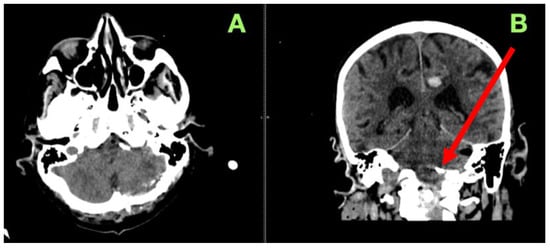

2. Case Presentation